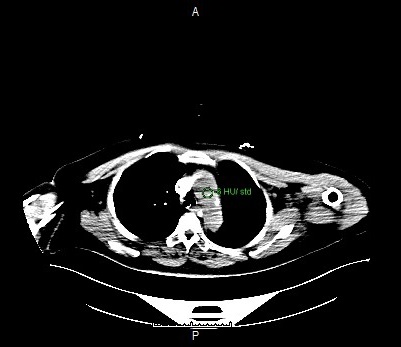

Post Contrast Scan Planning

Monitoring

- Single click on the pre-monitoring image

- Single click again to activate purple circle for triggering

- Drag and drop the circle inside the aortic arch region

- Click TRIGGERING tab

- Set the Hounsfield Unit value to 80

Setting the ROI circle for triggering